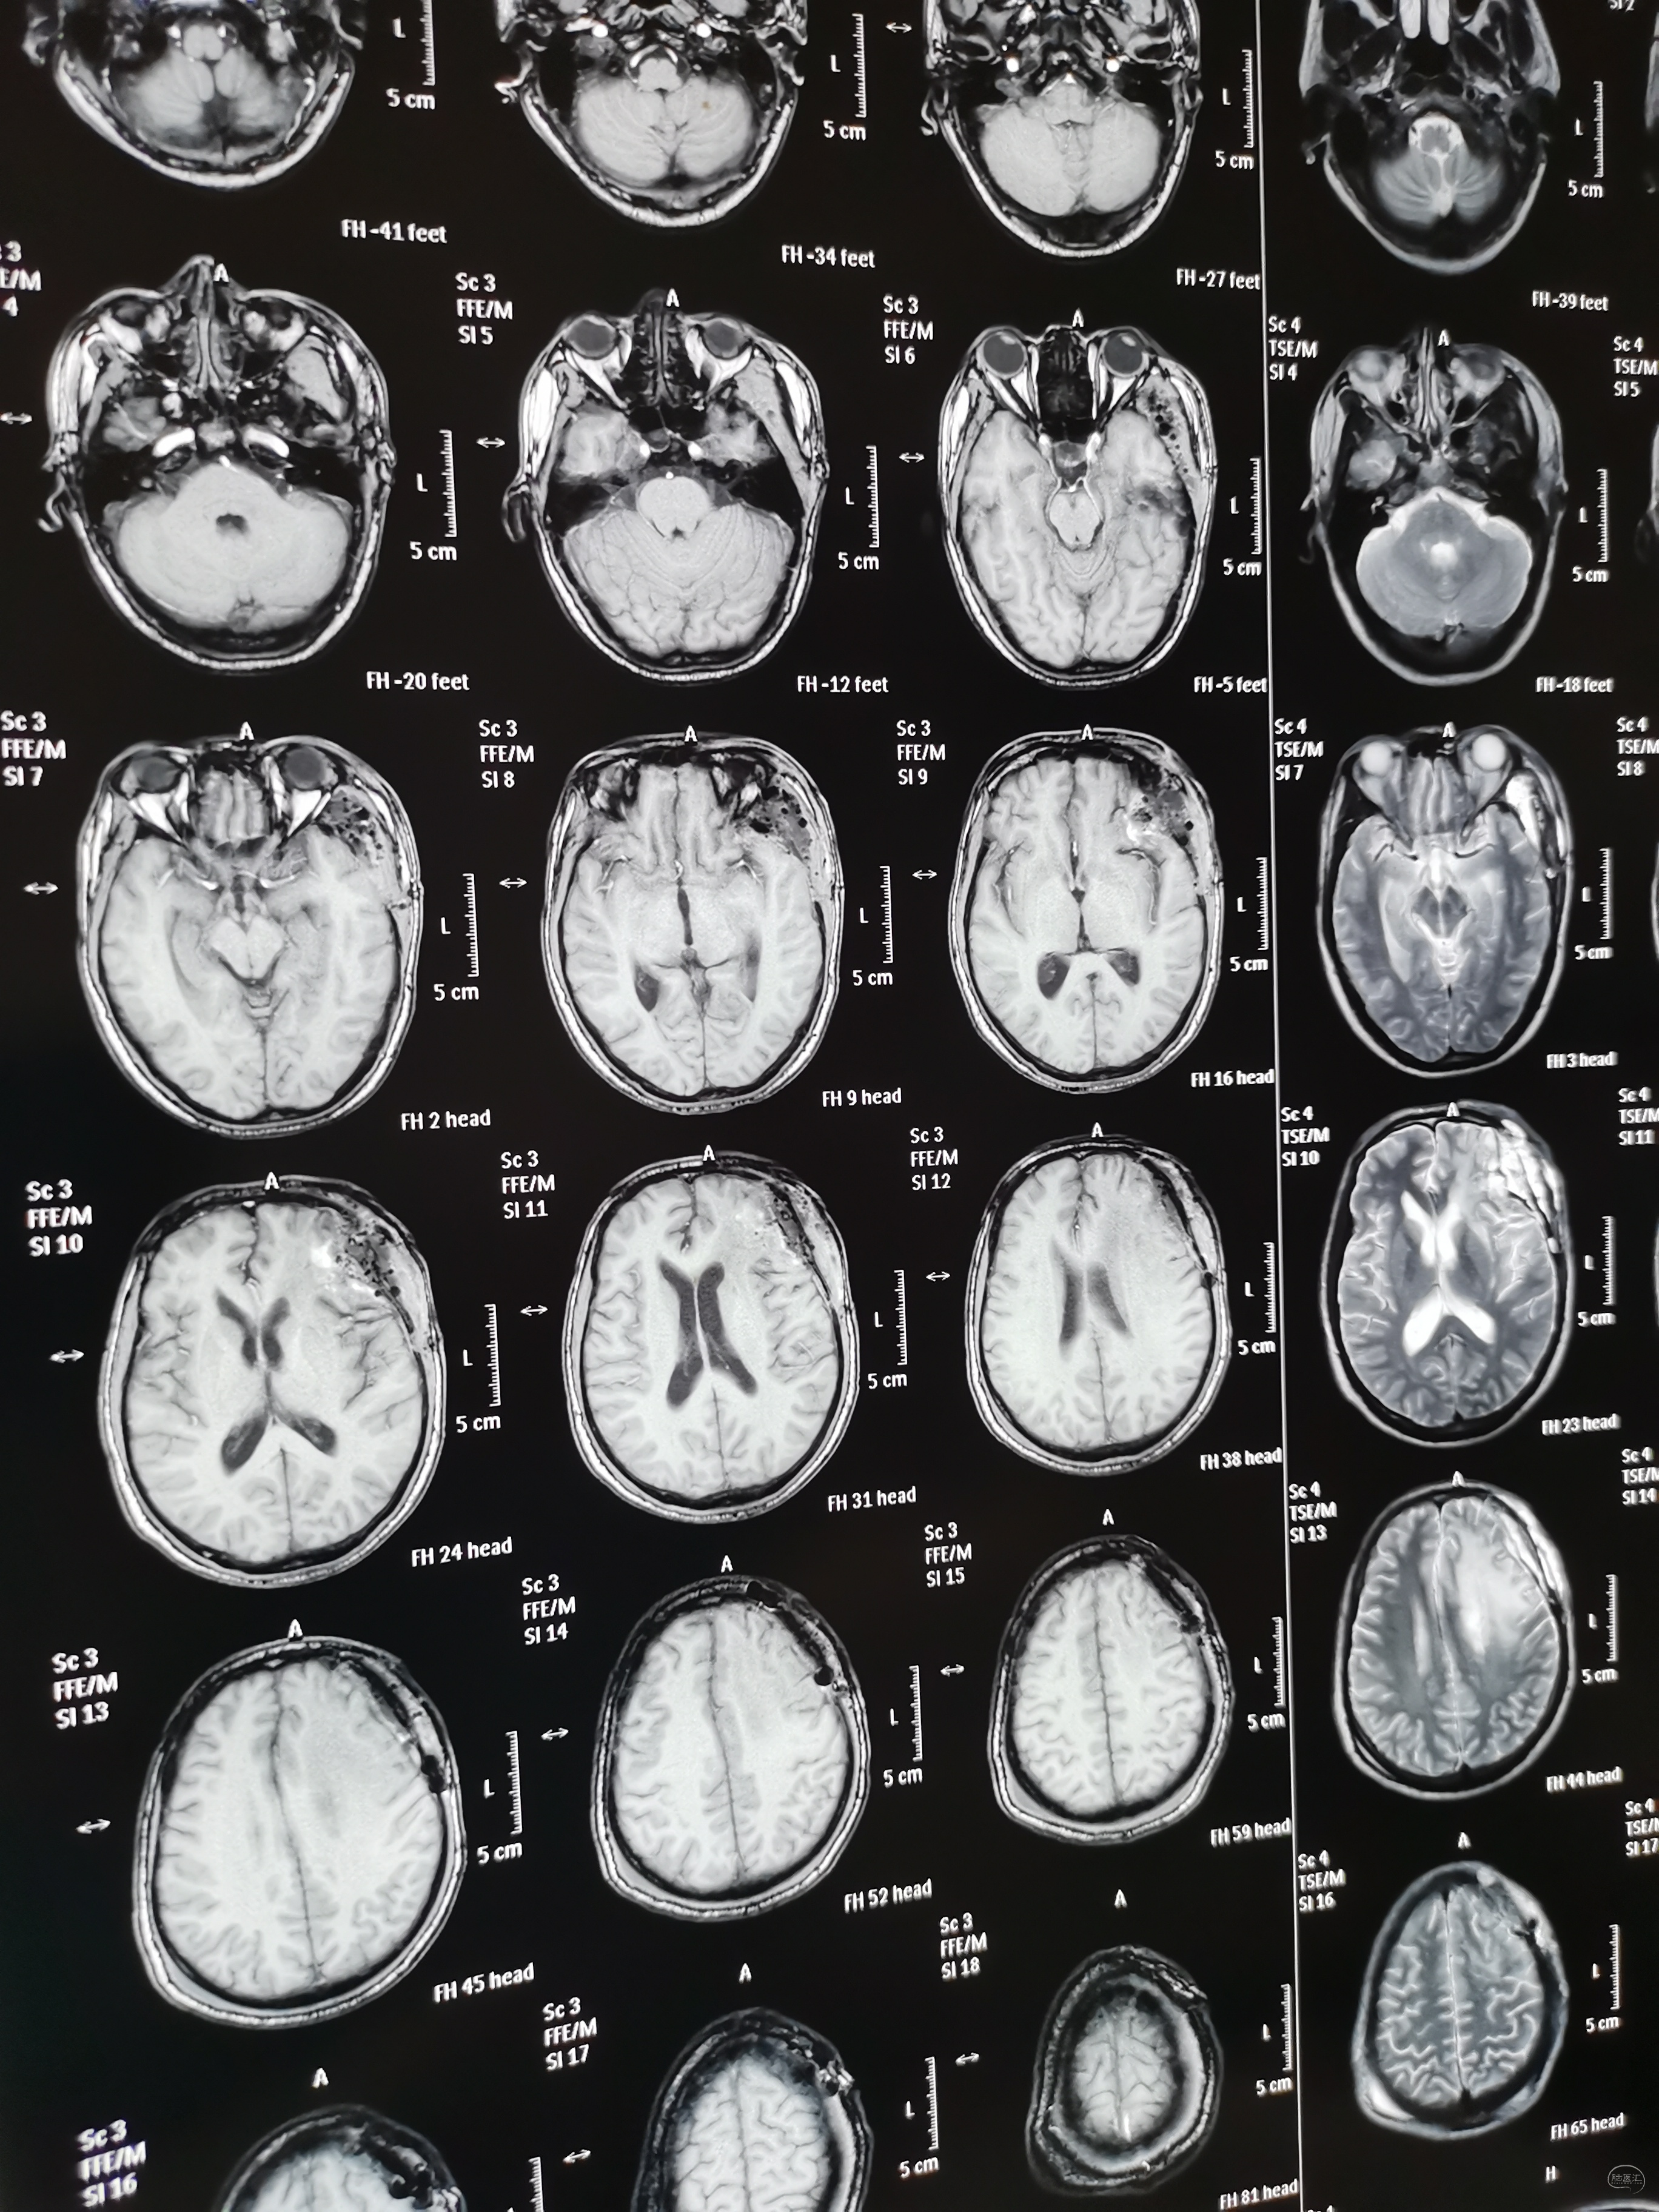

术前头颅MRI检查提示为左侧额叶占位性病变,增强强化均匀,似有脑膜征。考虑为脑膜瘤,蝶骨棘外侧型。

术后头颅MRI检查切除满意